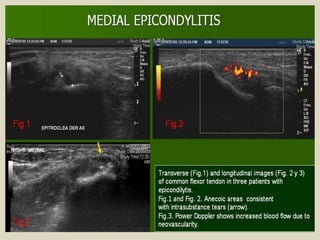

Medial epicondylitis also known as “golfer elbow” is

an overuse syndrome of the common flexor tendon. It is

thought to be due to repetitive micro trauma and results

in fibrosis. The ultrasound findings are comparable with

those of lateral epicondylitis.

The medial collateral ligament is injured in cases of

repeated valgus stress. It can be injured without damage

of the overlying common flexor tendon. Ultrasound may

demonstrate hypoechoic areas with fibrillar pattern

disruption, thickening or calcification of the ligament.